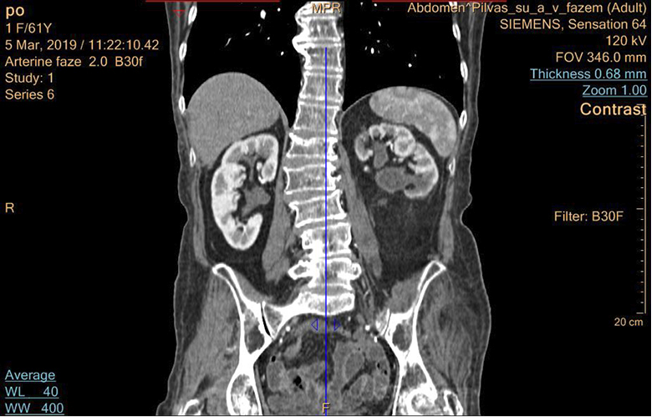

4 pav. Pacientės inkstų KT po operacijos praėjus dviem mėnesiams

Po mėnesio pacientei pašalintas endostentas iš kairiojo šlapimtakio. Pooperaciniu periodu pacientė kairiojo juosmens skausmų nejaučia, šlapinasi gerai. Pacientei likę minimalūs pooperaciniai randai (žr. 3 pav.). 2019-03-05 atlikta kontrolinė KT – kairiojo inksto geldelės prasiplėtimas sumažėjęs iki 19 mm (žr. 4 pav.). Tyrimuose – kreatininas (66 µmol).